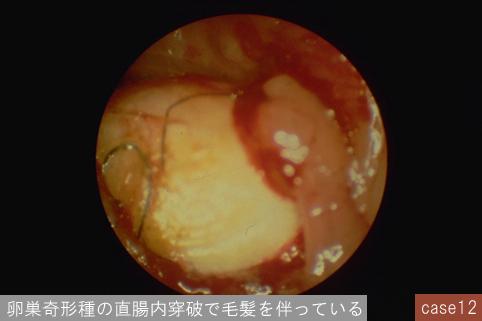

질환(병리주체)의 분류 기타/

부위(장기별) 대장/직장

검사방법 내시경

종양의 최대경(밀리미터) 30~34